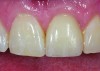

Fig 9. Custom healing abutment in place, with blanching present upon insertion.

Figure 9